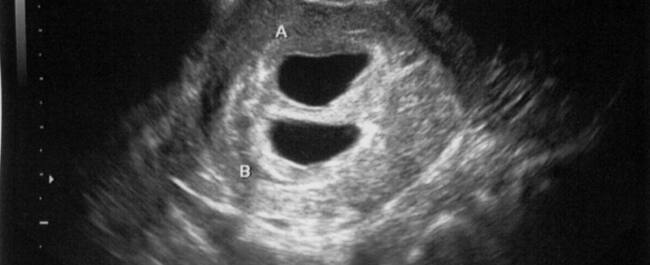

La Asociación El Defensor del Paciente se ha dirigido a la Fiscalía de Valladolid para que, de oficio, abra una investigación y depure las responsabilidades correspondientes por la incineración del cadáver de un feto sin autorización de sus padres en el Hospital Clínico Universitario.

La Consejería de Sanidad ha emitido un comunicado en el que informa que se ha actuado como dicta el protocolo, que se provocó el parto porque el feto estaba muerto y que tras 5 días en el depósito del Hospital fue enviado a incinerar, como se hace habitualmente en estos casos y que no se pudo comunicar a la madre que estaba en la UCI.